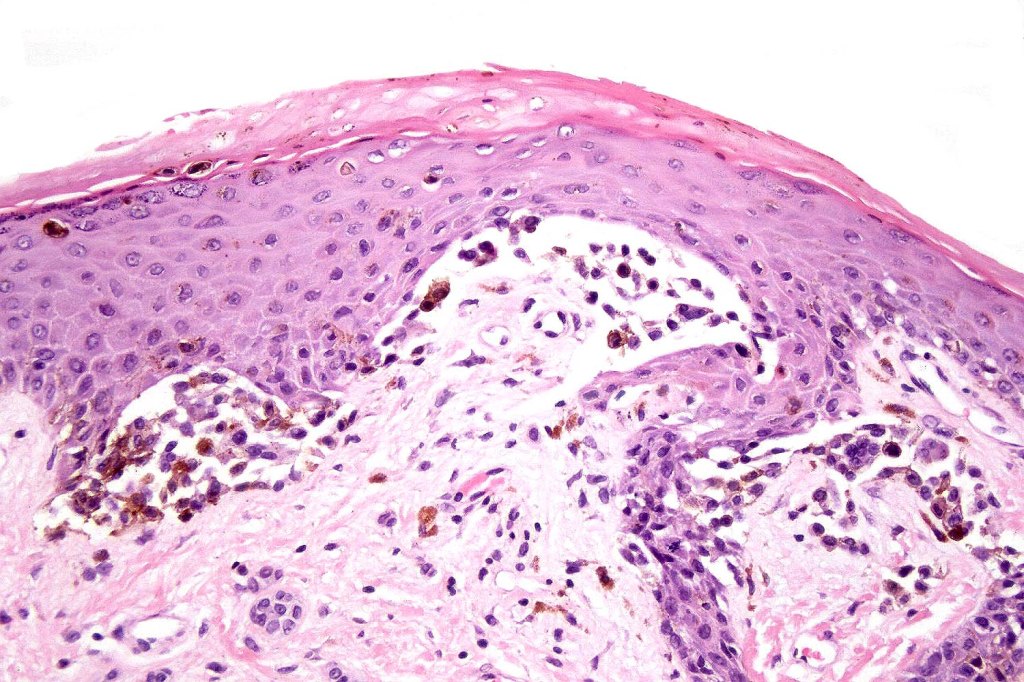

Histological features

•Large dyscohesive nests with retraction artifact, not restricted to the tips of the epidermal ridges

•Heavy pigmentation (sometimes gray/green)

•Dermal fibrosis (sometimes lamellar)

Most important is melanoma. Distinction is best afforded by the site of the nevus and the patient’s age. Vulval melanoma is generally a tumor of the elderly. Atypical genital nevus occurs in girls and young women.

There can be overlap with dysplastic nevi although the typical architecture of the latter is absent. Large, heavily pigmented, dyscohesive nests with a retraction artifact point towards atypical genital nevus. Knowing the site of the nevus is all important.